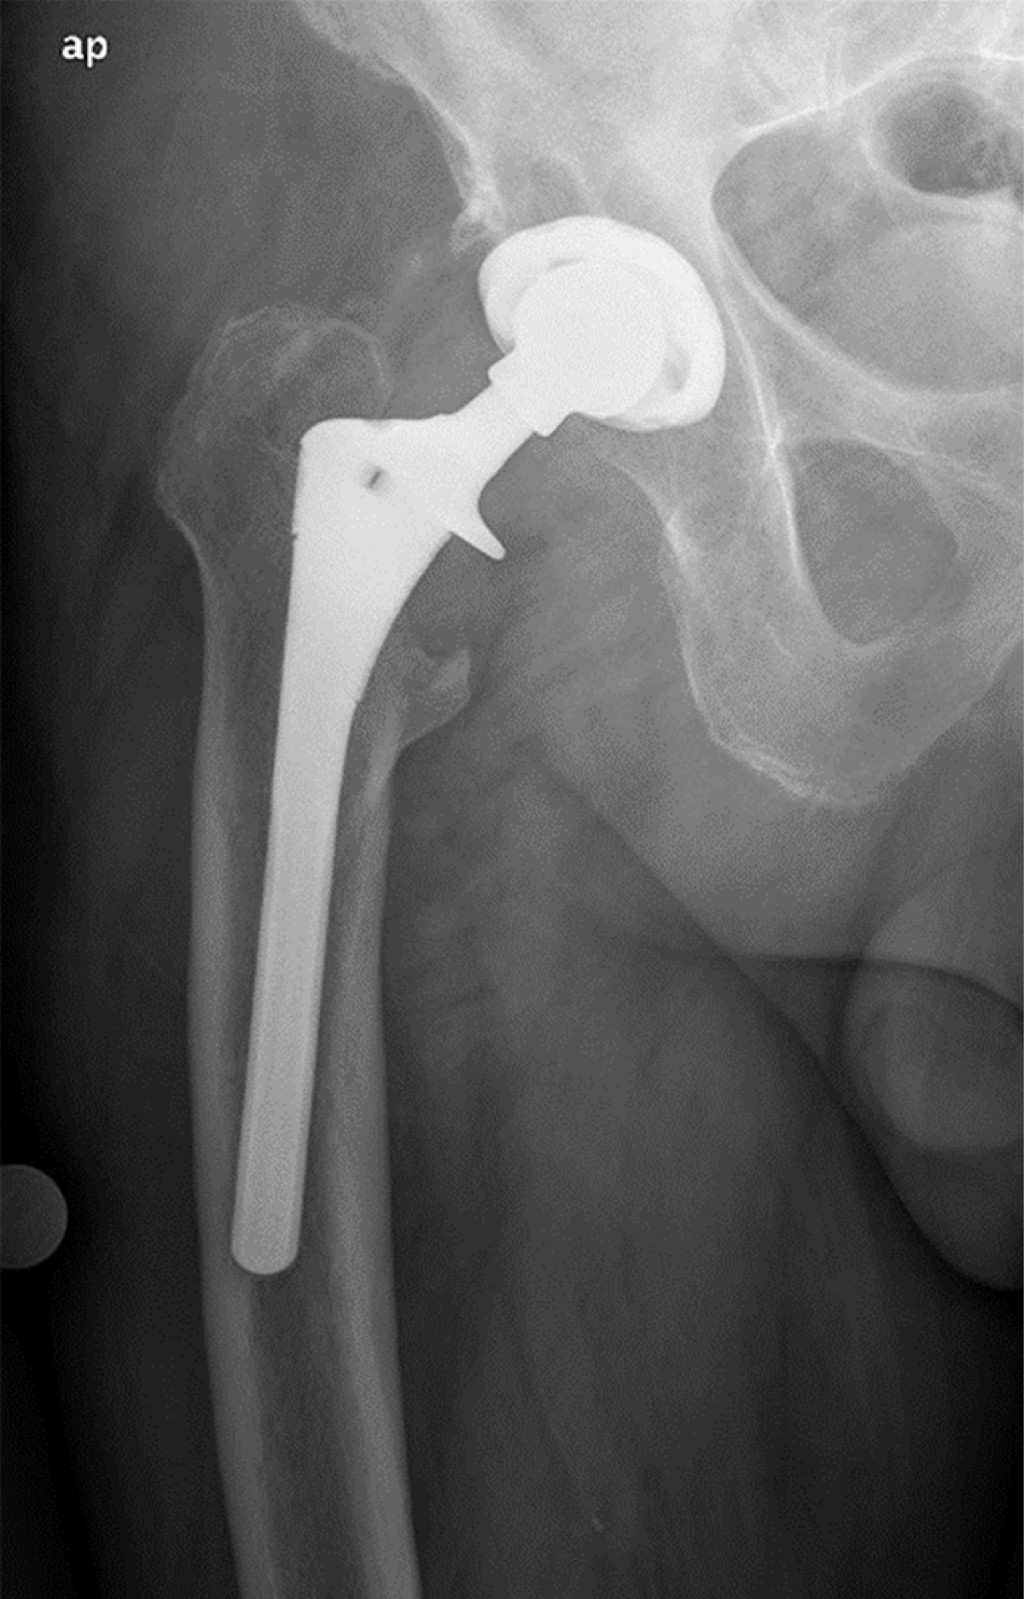

Minimizing risk: evaluation of the relationship between femoral stem loosening and the risk of presenting with peri-prosthetic hip fracture

Introduction: evaluation of predictors of periprosthetic fracture in loosened femoral stems. Material and methods: retrospective case-control study comparing aseptic loosened stems in two groups: cases: patients who experienced periprosthetic femoral fracture before replacement could be performed (n = 9). Controls: experienced prosthetic replacement without fracture (n = 19). Results: pain intensity (VAS) was the most important aspect (p = 0.01), predominating in the controls. The simple radiological parameters did not show statistically significant findings predictive of peri-prosthetic fracture (number of Gruen zones, sum of them in mm, stress shielding, pedestal, polyethylene wear, stem subsidence). The role of complementary tests (CT and scintigraphy) for the definitive diagnosis of loosening was relevant, but not significant. The type of implant showed no differences. Overall implant survival was higher in cases than in controls (p = 0.016). This difference continues when comparing each loosened stem until fracture or replacement (p = 0.024). Conclusion: the main factor protecting against fracture is the replacement of a stem with clinical and radiological diagnosis of loosening. Adequate follow-up of the patient plays a determining role in this, especially when considering the greater intensity of pain in the controls, which used to guide surgeons to perform replacements before the fracture occurred. This is reinforced if we take into account that up to one third of the cases did not have regular check-ups, and therefore did not have the opportunity for replacement prior to the fracture. The role of complementary tests (CT and scintigraphy) is also very important, taking into account the low diagnostic yield obtained from simple X-rays.

Figure 2